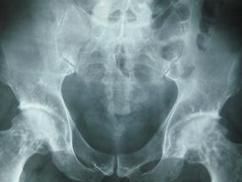

檢查

可行骨密度檢查和X線檢查。X線檢查可見關節軟骨下骨侵襲、骺生長板骨化異常或長骨變形。